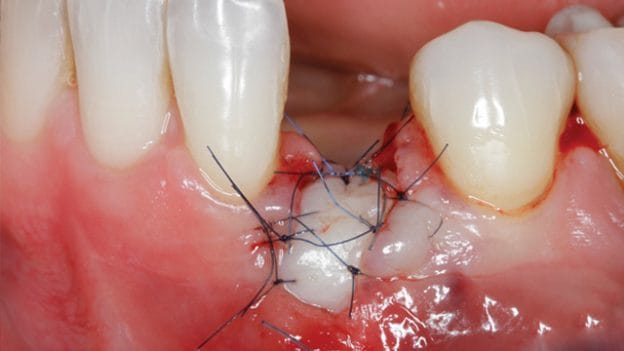

- Guided bone regeneration (GBR) by means of titanium mesh and onlay autologous block bone grafts (AOBG) for horizontal and vertical augmentation.

- How to approach and implement different surgical techniques, either used alone or in combination with autologous and/or heterologous graft materials to achieve alveolar bone augmentation (GBR and AOBG).